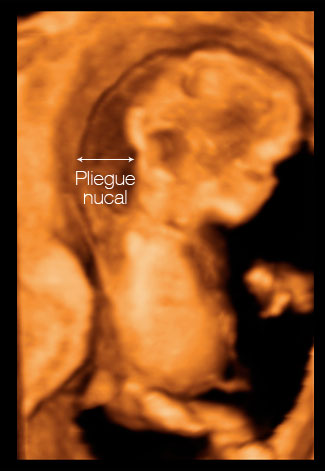

- La La medición de translucencia nucal o TN es un acúmulo de líquido en la zona cervical y dorsal posterior del feto que es observable antes de las 14 semanas y que posteriormente tiende a desaparecer. Su medición debe realizarse entre la semana 11+0 y 14+0, es decir, cuando el CRL se sitúa entre 45 y 84mm.

Se ha comprobado que la mayoría de los fetos con alteraciones cromosómicas como el síndrome de Down y un número significativo de los portadores de malformaciones graves (fundamentalmente cardiacas) tienden a acumular más líquido en esta región nucal. Por tanto, aunque no es posible descartarlo por completo, si la medición de la TN resulta normal, es muy poco probable que el feto esté afecto de síndrome de Down. Por el contrario, un aumento de la TN puede alertarnos de la posible existencia de algún problema que habrá que investigar a fondo.